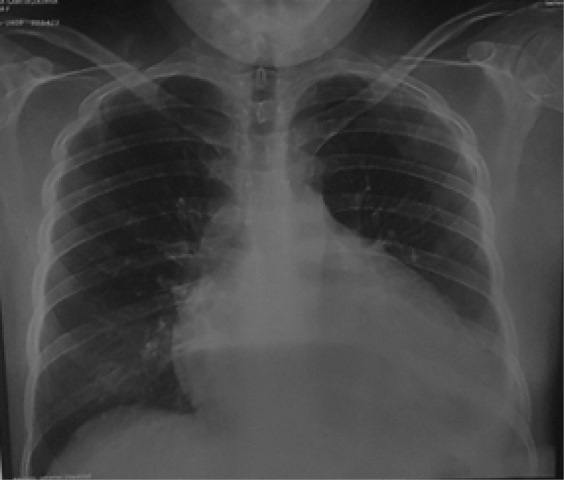

Radiografía de tórax (30/05/2020): se evidencia cardiomegalia III/IV con derrame pleural izquierdo. Partes óseas y blandas conservadas. Ver figura 1.